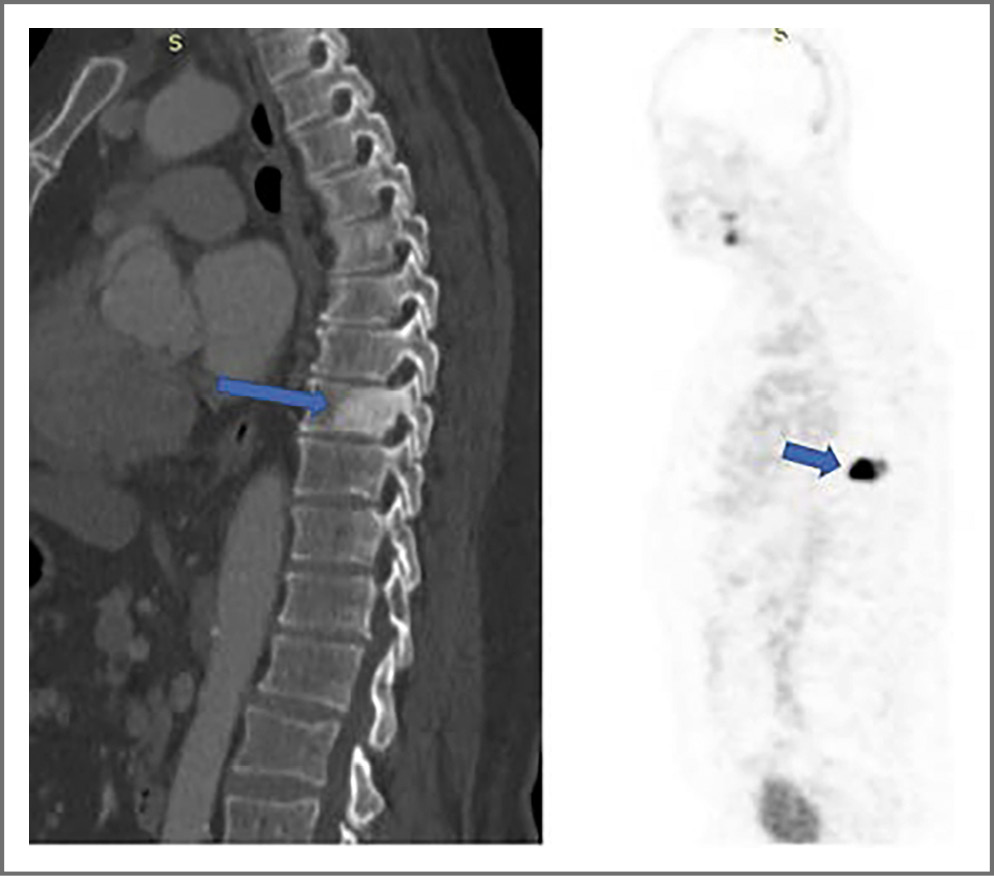

С февраля по декабрь 2021 г. отмечали рост ПСА с 0,27 до 10,05 нг/мл, в связи с чем пациенту выполнили МРТ органов малого таза, в результате убедительных данных за наличие зон с высокой целлюлярностью в зоне сканирования не получили. На рис. 2 (Т2-взвешенное изображение) зеленой стрелкой показано истончение (дефект) передней стенки прямой кишки, голубой – некоторое повышение сигнала от стенки и утолщение, возможно воспалительные изменения, желтой – пристеночное жидкостное содержимое. Пациенту назначили гормональную терапию (Золадекс 10,8 мг). Для уточнения признаков метастазирования рака простаты и необходимости ЛТ пациенту сделали позитронно-эмиссионную томографию, совмещенную с компьютерной томографией, по результатам которой на серии томограмм костной системы отмечается ПСМА-позитивный бластический метастаз в TIX [очаг размером 37×37 мм с SUV (Standardized Uptake Value – стандартизированный уровень захвата) 26 г/мл с накоплением радиофармпрепарата]; рис. 3. С учетом выявленного поражения позвоночника пациенту провели локальное стереотаксическое облучение TIX в режиме 3 фракций по 10 Гр, эквивалентная СОД 98,4 Гр, с положительным эффектом. Контрольный уровень ПСА стал в референсных значениях.

Рис. 3. Позитронно-эмиссионная томография, совмещенная с компьютерной томографией, от 14 февраля 2022 г. Метастаз тела TIX позвонка.

Fig. 3. Positron emission tomography, February 14, 2022. Metastasis of the TIX vertebral body.